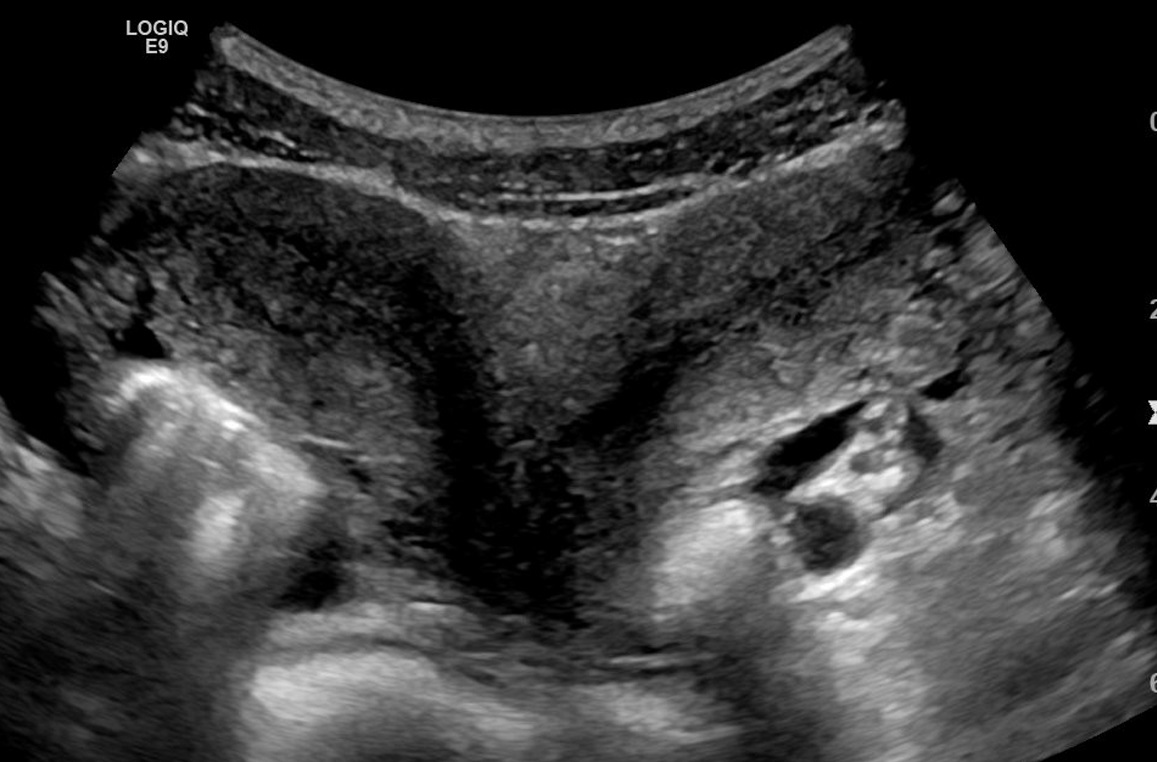

자궁 기형은 여성의 자궁 구조에 이상이 있는 상태를 의미하며, 일반 인구의 약 6.7%에서 나타난다. 미국생식의학회(ASRM)는 자궁 기형을 뮐러관 무발생, 단각 자궁, 중복 자궁, 쌍각 자궁, 자궁 중격, DES 자궁 등 6가지 유형으로 분류한다. 진단은 초음파, MRI, 자궁난관조영술 등의 영상 기술을 통해 이루어지며, 자궁 중격과 같은 특정 기형은 수술로 치료할 수 있다.

신체 검사 외에도 의사는 기형의 정확한 특징을 파악하기 위해 영상 기술을 활용한다. 주로 사용되는 영상 기술에는 부인과 초음파 검사, 골반 MRI, 또는 자궁난관조영술이 있다. 하지만 자궁난관조영술은 자궁의 외부 윤곽을 평가하기 어렵고, 쌍각 자궁과 중격 자궁을 구별할 수 없다는 한계 때문에 유용성이 떨어진다고 여겨진다.